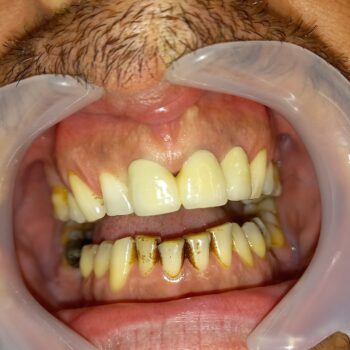

Η σημασία της προσωρινής αποκατάστασης κατά τη διάρκεια προσθετικής εργασίας